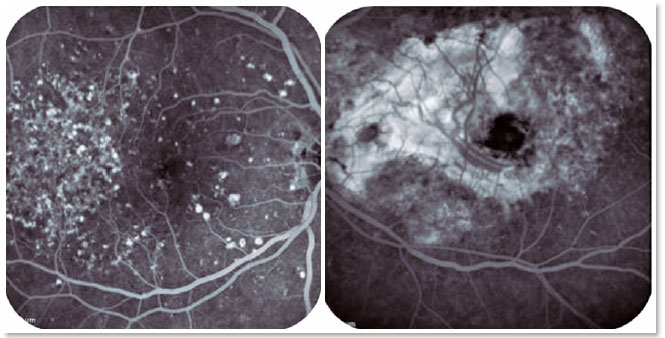

In view of the clinical findings, she underwent a complementary diagnostic investigation for better evaluation. Fluorescein angiography revealed several hyperfluorescent spots affecting the entire macular region of the OD due to contrast impregnation in the drusen, and an extensive area of hyperfluorescence with contrast tissue impregnation in the macular region of the OS, consistent with a disc-shaped scar secondary to SRNVM (Figure 2). Autofluorescence examination revealed hyperautofluorescent spots in the macular region of the OD and a hypoautofluorescent area indicating retinal atrophy in the macular region of the OS (Figure 3). Full-field electroretinogram was inconclusive, and electro-oculogram presented macular and cone functional impairment in OU. Optical coherence tomography (OCT) revealed focal, hyper-reflective, subepithelial lesions suggestive of drusen in the macular region of the OD. In the OS, OCT revealed an extensive hyper-reflective area associated with disorganization of the retinal layer microarchitecture, suggestive of fibrotic scar tissue (Figure 4). Further, OCT showed no changes in the optic disc.